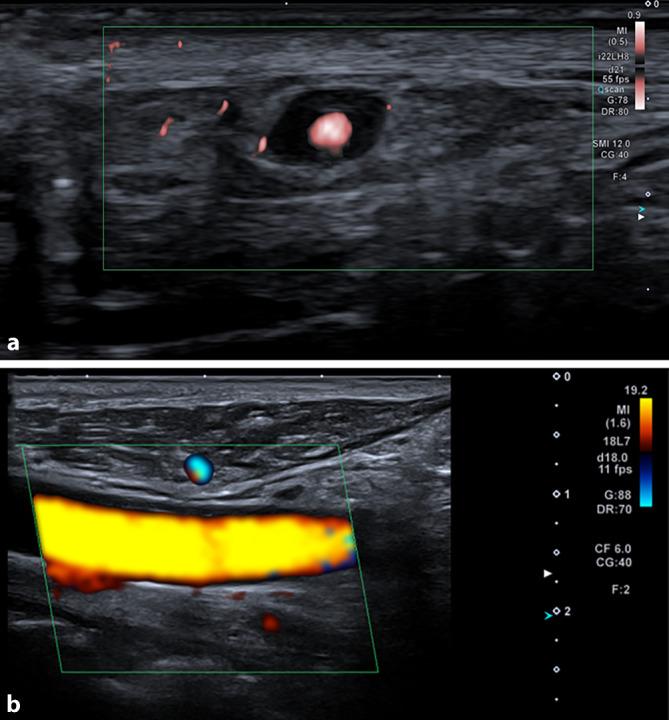

An 83-year-old male patient presented due to a 3-week history of swelling of the tongue with tongue pain on eating, yellowish plaques, and a gray-brown lesion in the anterior portion of the tongue. Sudden loss of vision in the left eye and temporal headache occurred 3 days before presentation. Due to elevated C‑reactive protein, sonography of the supraaortic arteries as well as positron emission tomography/computed tomography was performed. Imaging revealed inflammation of the great arteries as well as a halo sign on ultrasound of the temporal artery. Thus, a diagnosis of giant cell arteritis with necrosis of the tongue was made. Immunosuppressive therapy with glucocorticoids was initiated. Necrosis of the tongue is a rare manifestation of giant cell arteritis that requires immediate immunosuppressive therapy to prevent further complications to the tongue (e.g., complete necrosis of the tongue, superinfection, tongue amputation).

一名83岁男性患者因舌头肿胀3周就诊,进食时伴有舌痛、黄色斑块,舌前部有灰棕色病变。就诊前3天出现左眼突然失明和颞部头痛。由于C反应蛋白升高,进行了主动脉弓上动脉超声检查以及正电子发射断层扫描/计算机断层扫描。影像学检查显示大动脉炎症以及颞动脉超声上的晕征。因此,诊断为巨细胞动脉炎伴舌坏死。开始使用糖皮质激素进行免疫抑制治疗。舌坏死是巨细胞动脉炎的一种罕见表现,需要立即进行免疫抑制治疗以防止舌头出现进一步并发症(如舌完全坏死、二重感染、舌截肢)。